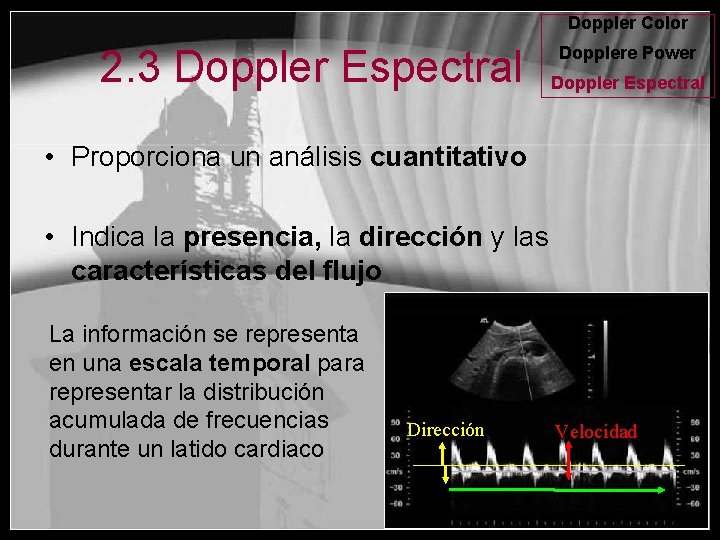

Doppler Color 2. 3 Doppler Espectral Dopplere Power Doppler Espectral • Proporciona un análisis cuantitativo • Indica la presencia, la dirección y las características del flujo La información se representa en una escala temporal para representar la distribución acumulada de frecuencias durante un latido cardiaco Dirección Velocidad